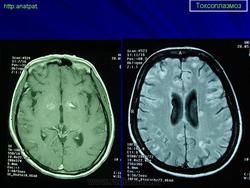

Токсоплазмоз

Церебральный токсоплазмоз.

Церебральный токсоплазмоз